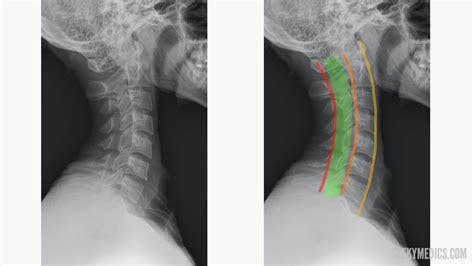

Interpreting a Normal Neck X Ray

Interpreting a Normal Neck X Ray involves examining the images for any abnormalities. Key structures to assess include:

• Vertebrae: The seven cervical vertebrae (C1-C7) should be clearly visible and aligned.

• Intervertebral Discs: The spaces between the vertebrae should be uniform and without narrowing.

• Joints: The facet joints should be well-defined and without signs of degeneration or inflammation.

• Soft Tissues: The soft tissues, including muscles and ligaments, should appear normal without any swelling or masses.

In a Normal Neck X Ray, the following features are typically observed:

Structure Normal Appearance

Vertebrae Well-defined, aligned, and without fractures or deformities.

Intervertebral Discs Uniform spaces between vertebrae, without narrowing or herniation.

Joints Smooth and well-defined, without signs of arthritis or inflammation.

Soft Tissues No swelling, masses, or other abnormalities.

• Kyphosis: A slight forward curvature of the cervical spine, which is normal in some individuals.

• normal neck curvature x ray